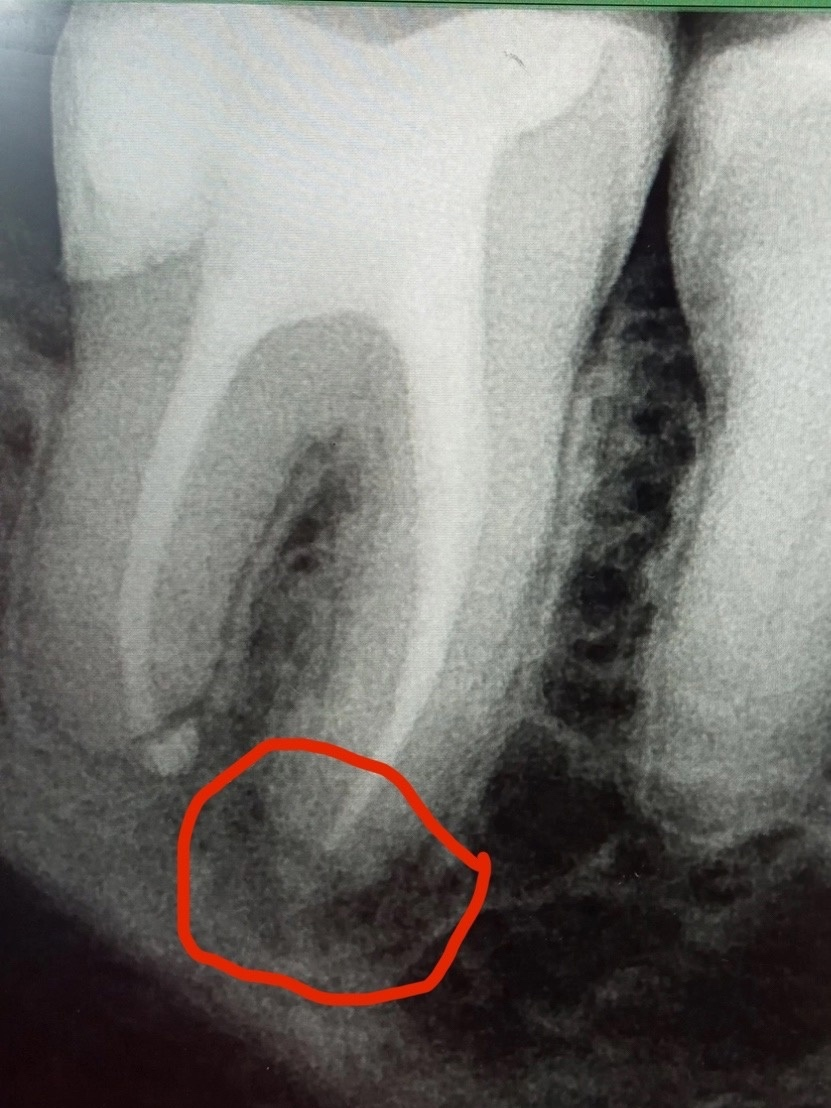

annda Опубликовано 9 марта, 2025 Поделиться Опубликовано 9 марта, 2025 (изменено) А снимок изначальной ситуации есть? Вы когда вообще его лечили? Может, у вас там очаг был в два раза больше , а это стадия заживления идет. Она от 6 мес до 5 лет продолжается, вообще то. Никто такой вариант не рассматривал? Вот поэтому и нужно КТ и до первого лечения иметь, и до второго! в динамике так сказать. Чтобы сравнивать результаты и избежать вот этих вот метаний. Сразу такие очаги не заживают. И при желании и должной тревожности можно хоть каждый год перелечивать:)) Коффердам- обязателен, микроскоп - опция , конечно, но контролировать степень очистки канала без него практически невозможно, это просто факт. Изменено 9 марта, 2025 пользователем annda Ссылка на комментарий

Pawa213123 Опубликовано 10 марта, 2025 Автор Поделиться Опубликовано 10 марта, 2025 В 09.03.2025 в 09:19, annda сказал: А снимок изначальной ситуации есть? Вы когда вообще его лечили? Может, у вас там очаг был в два раза больше , а это стадия заживления идет. Она от 6 мес до 5 лет продолжается, вообще то. Никто такой вариант не рассматривал? Вот поэтому и нужно КТ и до первого лечения иметь, и до второго! в динамике так сказать. Чтобы сравнивать результаты и избежать вот этих вот метаний. Сразу такие очаги не заживают. И при желании и должной тревожности можно хоть каждый год перелечивать:)) Коффердам- обязателен, микроскоп - опция , конечно, но контролировать степень очистки канала без него практически невозможно, это просто факт. 3D снимка изначальной ситуации нет, но есть обычный. И на обычном снимке все хорошо. Что мы лечили? Я пришел с сильной болью в зубе к врачу. Был под подозрением один зуб, который выглядел нормально на прицельном снимке. Тем не менее, мы его раскрыли и обнаружили, что нерв по какой-то причине гниет. Удалили нерв, вылечили зуб. Через пару месяцев обнаружили воспаление вокруг верхушки корня. У меня есть несколько прицельных снимок с воспалением и один 3D снимок, сделанный пол года назад Ссылка на комментарий

annda Опубликовано 10 марта, 2025 Поделиться Опубликовано 10 марта, 2025 Нужен тот самый 3д снимок ( КТ) до лечения и сейчас. Ваш рассказ- это ваша вольная интерпретация событий и ни о чем никому тут не скажет точно о вашем диагнозе. 1 Ссылка на комментарий

Pawa213123 Опубликовано 12 марта, 2025 Автор Поделиться Опубликовано 12 марта, 2025 (изменено) 17 часов назад, annda сказал: Какая цель перелечивания сегодня. Жалобы?Протезирование? Перелечить хочу, так как изредка чувствую небольшую и терпимую боль в этом районе. Да и даже если отбросить боль, неправильно же бездействовать, когда такое воспаление находится в районе зуба? А то не дай Боже разрастется и в костную челюсть зайдет гной. Не дай Бог сепсис случится или еще что. На этом же форуме мне скидывали ссылочку, как опасно ходить с воспалением вокруг верхушки корня, даже если оно маленькое. В-общем цель проста: избавиться от воспаления, чтобы не параноить, что оно в будущем аукнется Изменено 12 марта, 2025 пользователем Pawa213123 Ссылка на комментарий